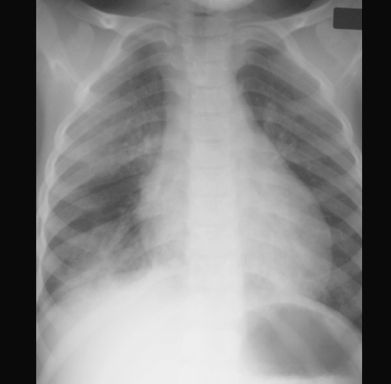

OBRZĘK PŁUC

RTG